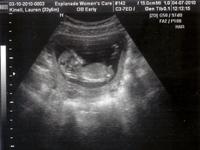

In the Belly (22 Pics)

3D Baby in Belly Video -- 3/10/2010